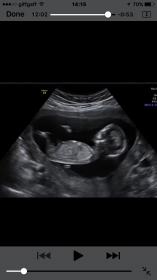

she would love to have your guesses!! She was 13.5 weeks at the scan.

I have gone through her whole video! I can only get these.... any insight at all? XX

I'm going boy from looking at that video; I've screenshot 3 clips that show an angled nub and stacking x